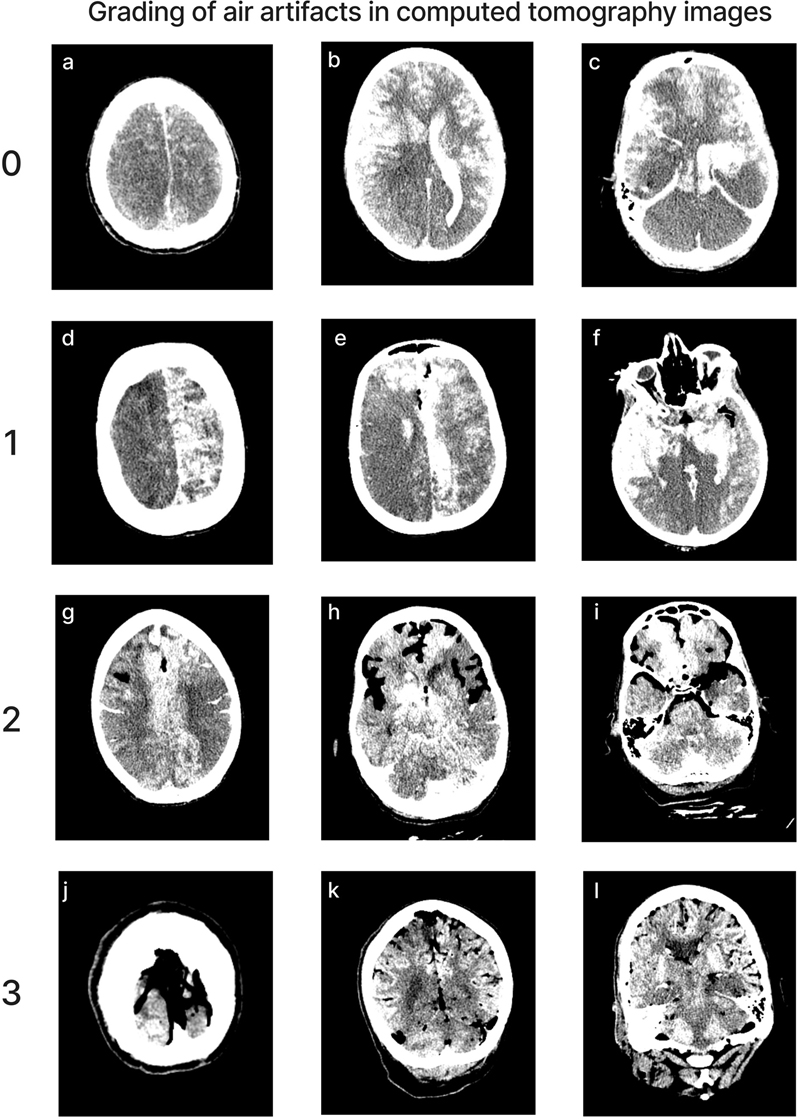

CT images

We aimed to perform neuroimaging both before and after perfusion, with the brain remaining inside of the skull. The CT scanner we used was the OmniTom® Elite (Neurologica, Danvers, MA), a 16-slice scanner. Images were viewed with the Osimis Web Viewer. Occasionally, one or both of these CT scans was not performed, for example if the CT scanner was not working at the time. For each of eight major vascular territories – corresponding to the territory supplied by the left and right anterior cerebral artery (ACA), middle cerebral artery (MCA), and posterior cerebral artery (PCA), as well as the cerebellum, we graded the extent of contrast visualized on the post-perfusion CT scans in a given territory on a 0–3 scale, with 0 indicating < 5 % extent of perfusion, 1 indicating 5–50 %, 2 indicating 50–95 %, and 3 indicating > 95 %. In some cases, the grades could not be completed for some of the areas in the brain because the available CT scan contained only part of the brain, not the whole brain. The extent of air bubbles in the CT scan across the brain was also graded on a 0–3 scale, with 0 indicating no apparent air bubbles, 1 minimal, 2 moderate, and 3 substantial. This grading was performed on all of the post-perfusion CT scans available via the collaboration of two graders. For a brain-wide assessment measure, we generated a separate score based on the sum of the grades across all evaluated areas, excluding cases with missing data from any vascular territory.

Quality of perfusion in CT images

Perfusion quality based on CT scans was graded on a semi-quantitative scale, reflecting the estimated percentage of contrast agent present in different brain regions (Figure 4). We also developed a semi-quantitative grading scale to assess the extent of air bubbles observed in some CT scans (Figure 5). For a subset of cases, the images were graded separately by two independent raters, yielding an ICC of 0.536 (95 % CI: 0.293–0.705), indicating fair interrater reliability. Consistent with the observations from gross examination images, the CT scans revealed patchy distribution of contrast in nearly all cases, both across and within vascular territories.

Figure 5.

Representative images of CT scans showing the grading of air bubble extent across the brain. Donor IDs: 202 (a, b, c), 207 (d, e, f), 184 (g, h, i), 160 (j, k, l).